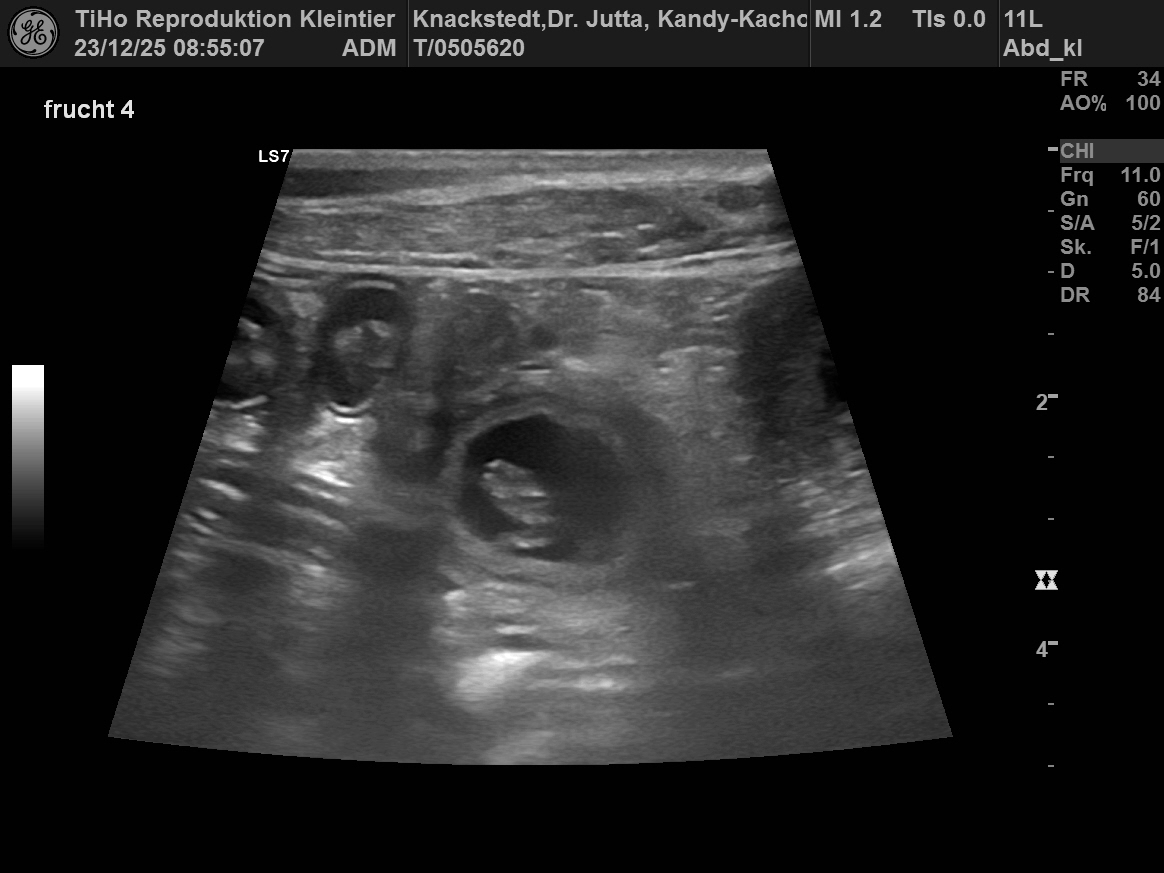

23. Dezember 2025

Der Ultraschall hat es bestätigt,

Wir erwarten Ende Januar 2026 unsren N-Wurf.